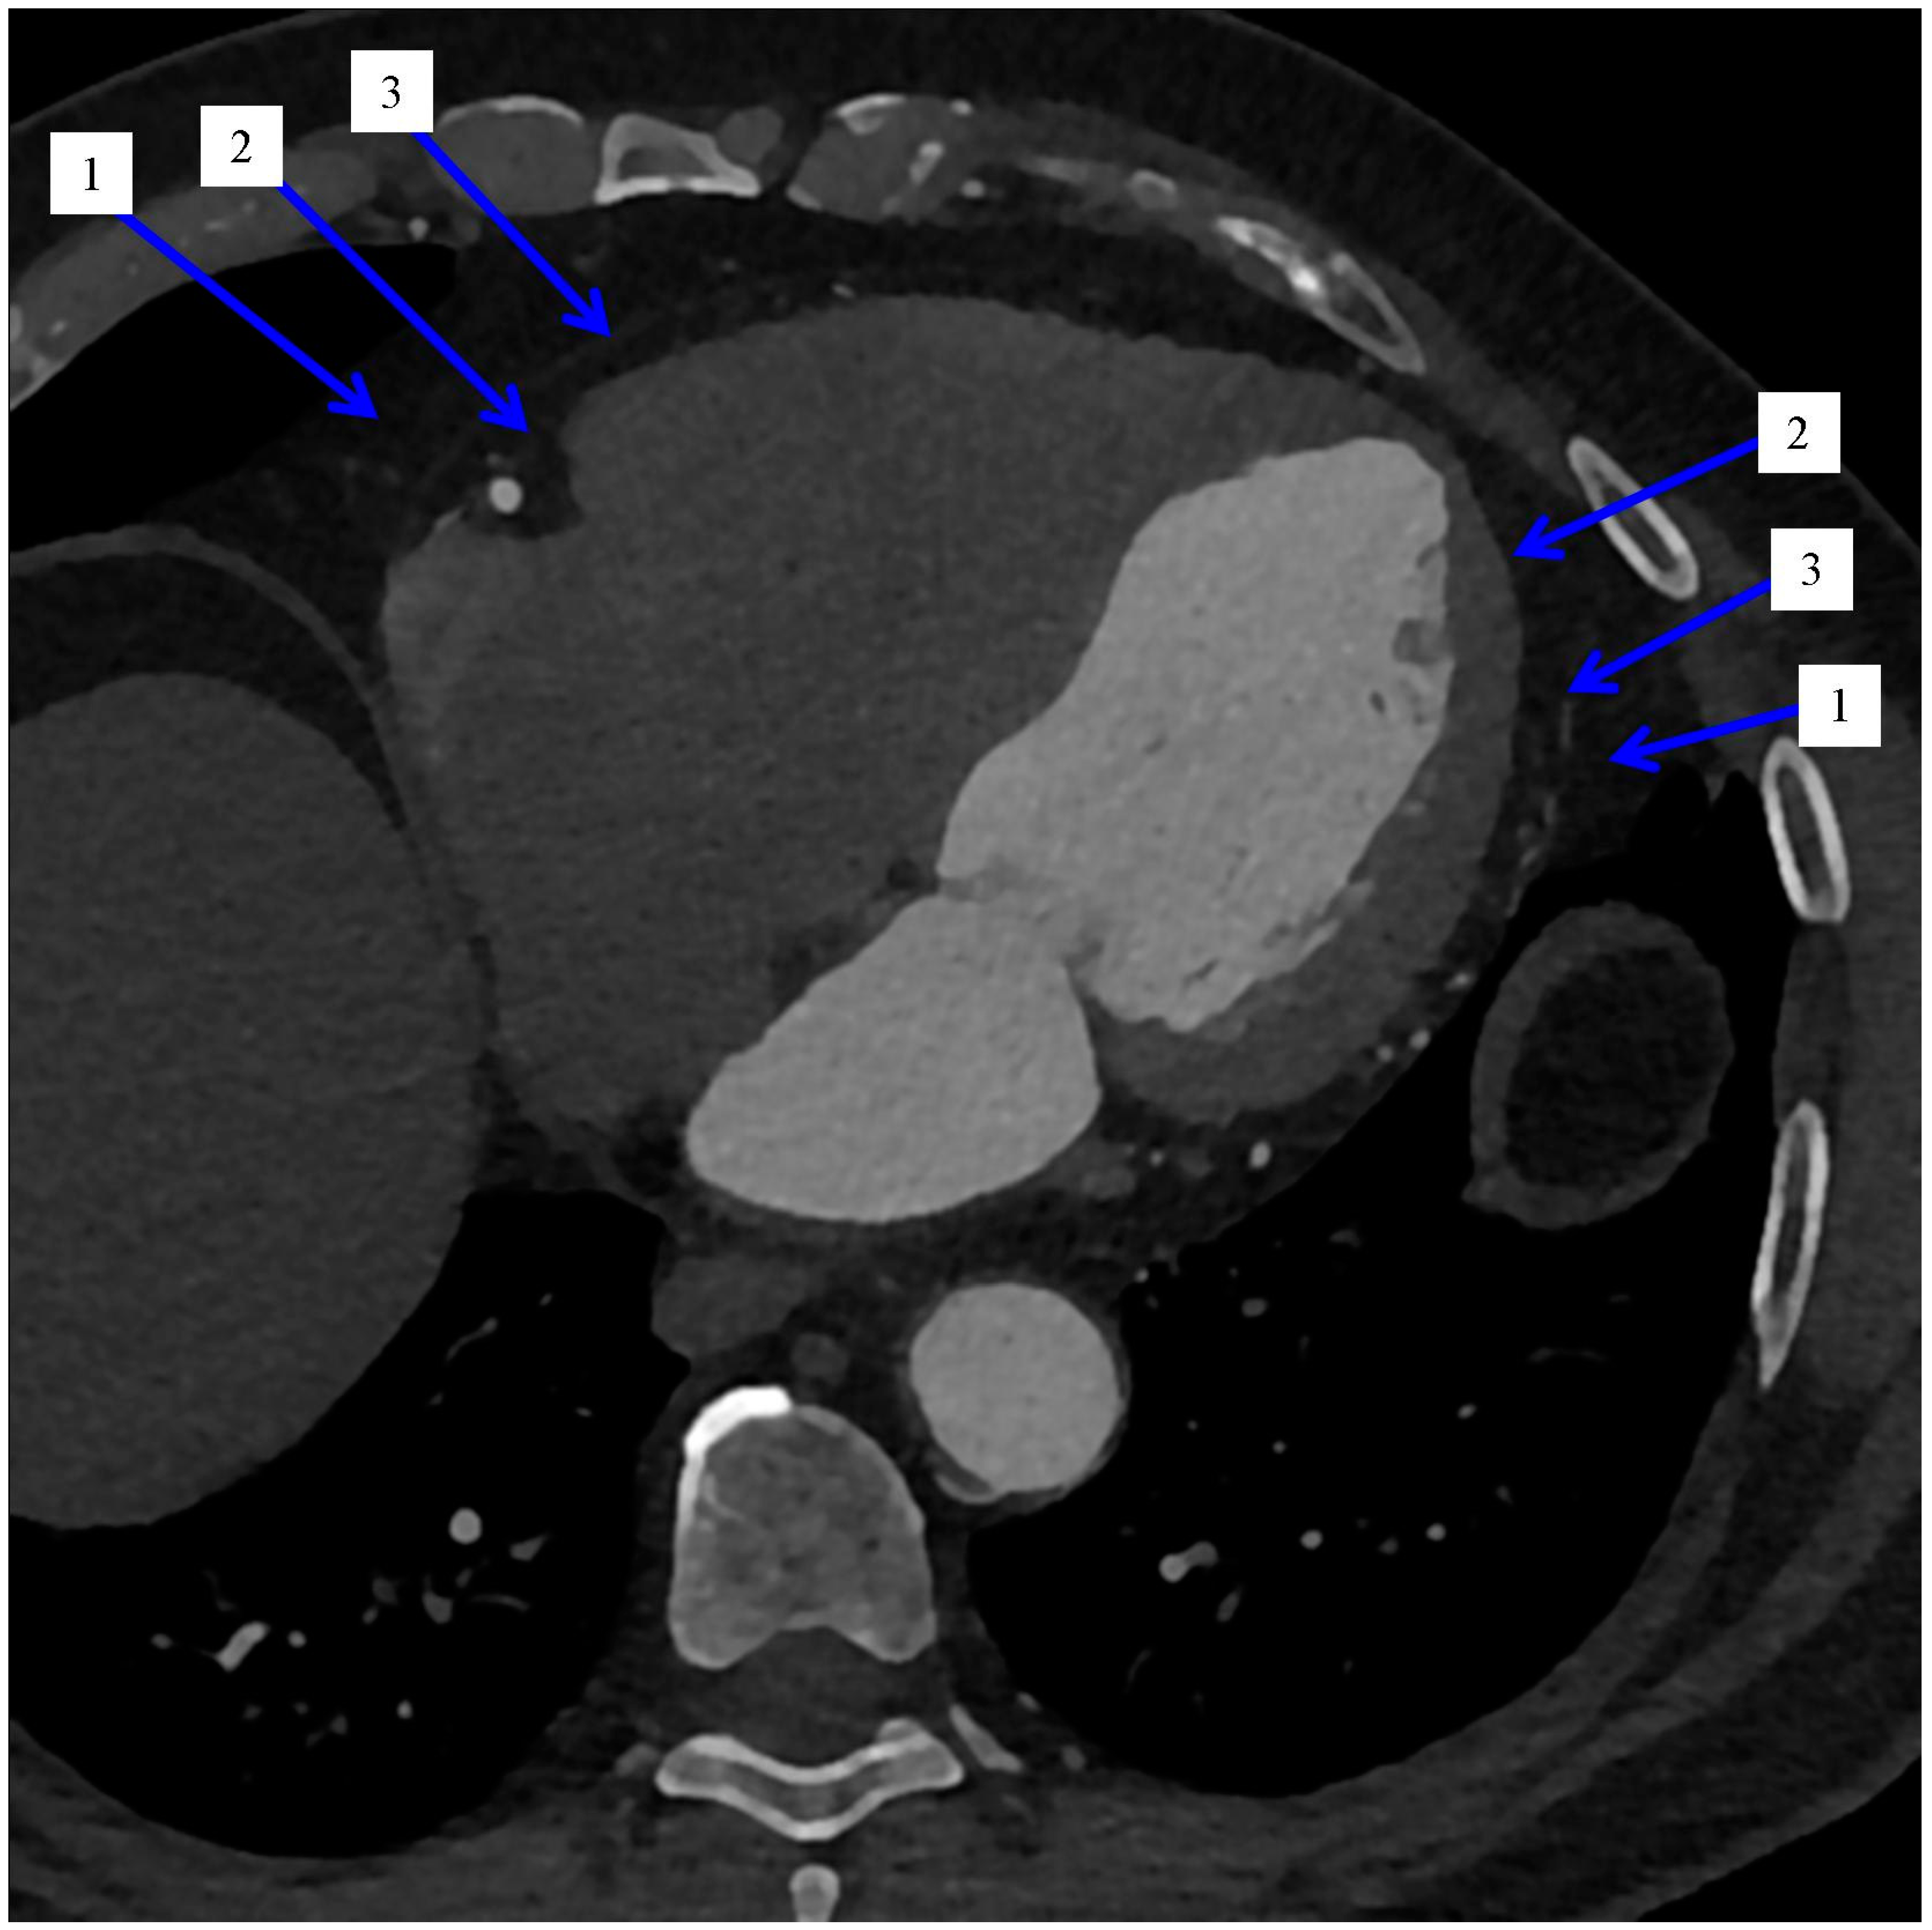

2.1. Distribution of the Epicardial Adipose Tissue

2.2. Imaging and Measurement Methods of Epicardial Adipose Tissue